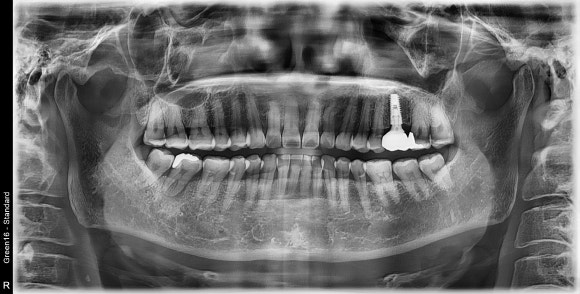

두번 째 환자 입니다.

사진 상 왼쪽 아래 두번 째 어금니 치근단 농양

위 파노라마 사진의 실제 구강 내 사진

사진 상 왼쪽 맨 끝에서 두번 째 어금니 뿌리 주변으로

뼈가 녹아내리고 있는 것을 볼 수 있습니다.

실제 구강 내 사진에서는 붓기가 관찰 됩니다.

해당 케이스의 경우 치아의 모빌리티가 매우 심했으며,

누르는 순간 치아가 움푹 움푹 들어가고 노란 농 (PUS)의 배출도 관찰 되었습니다.

증상은 없어서 환자가 심각한 정도인지 인지를 하지 못했지만,

저를 신뢰하시는 분이었기 때문에

미리 발치를 하여 감염이 더 퍼지지 않도록 방지를 한 케이스 입니다.

빠른 발치가 중요한 이유는, 최대한 뼈와 치주조직의 파괴를 방지하면

본인 본연의 뼈의 보존으로 인하여

추 후, 임플란트 치료가 더 쉽고 예후가 좋을 수 있기 때문입니다.